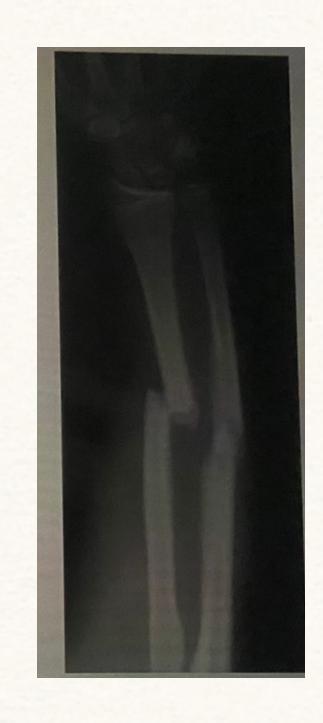

Case: A man involved in a road traffic accident (RTA) where a car ran over his forearm. X-ray showed fracture of the forearm.

Diagnosis?

- Compartment syndrome

What are the clinical features?

- The 5 Pโs:

- Pallor

- Paresthesia

- Pain (out of proportion to injury)

- Paralysis

- Pulselessness

Management?

- ABCโs (Airway, Breathing, Circulation)

- Correct hypotension

- Remove circumferential bandages & cast

- Position limb at level of the heart

- Supplemental oxygen

- Fasciotomy (definitive treatment)